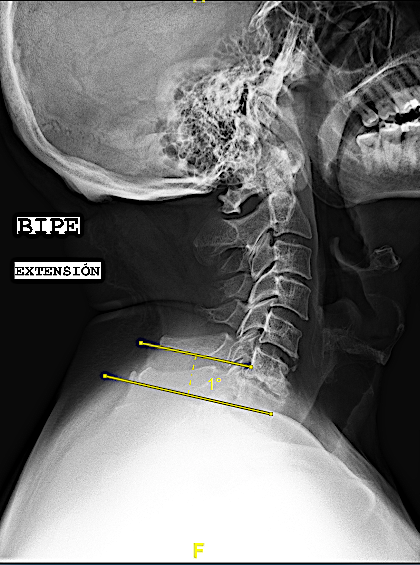

- «fijación intersomática» cuando en las RX funcionales no se aprecia movimiento sin ver «puentes óseos». Puede valer para este apartado el criterio de hallar una diferencia de <1mm entre la distancia de las respectivas apófisis espinosas en flexo/extensión o, si las espinosas no se visualizan o no están presentes, una angulación de platillos <3º también en las RX dinámicas. A estos pacientes les realizo un seguimiento anual con Rx (hasta visualizar puentes óseos o durante 3 años).

Las RX dinámicas demuestran fijación intersomática sin puentes óseos todavía. Obsérvese la recuperación del espacio intersomático respecto al preoperatorio, (indicativo de estabilidad de la artrodesis). El paciente, a los 6 meses de la cirugía, refiere crisis frecuentes de cervicalgias mecánicas altas bien controladas con analgesia de primer nivel y reposo relativo (ha dejado mórficos) y resolución de la braquialgia izquierda.